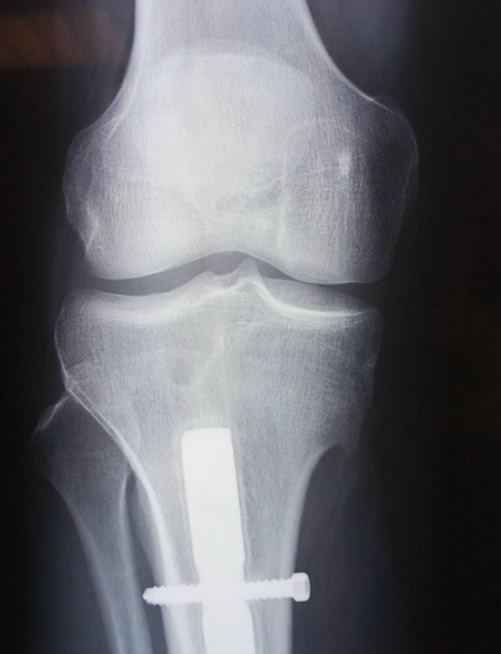

Le realizamos estudio Rx no hallando daño aparente en el mismo. Se puede ver parte del clavo de titanio que le implantamos en la tibia a principio de la temporada 2008.